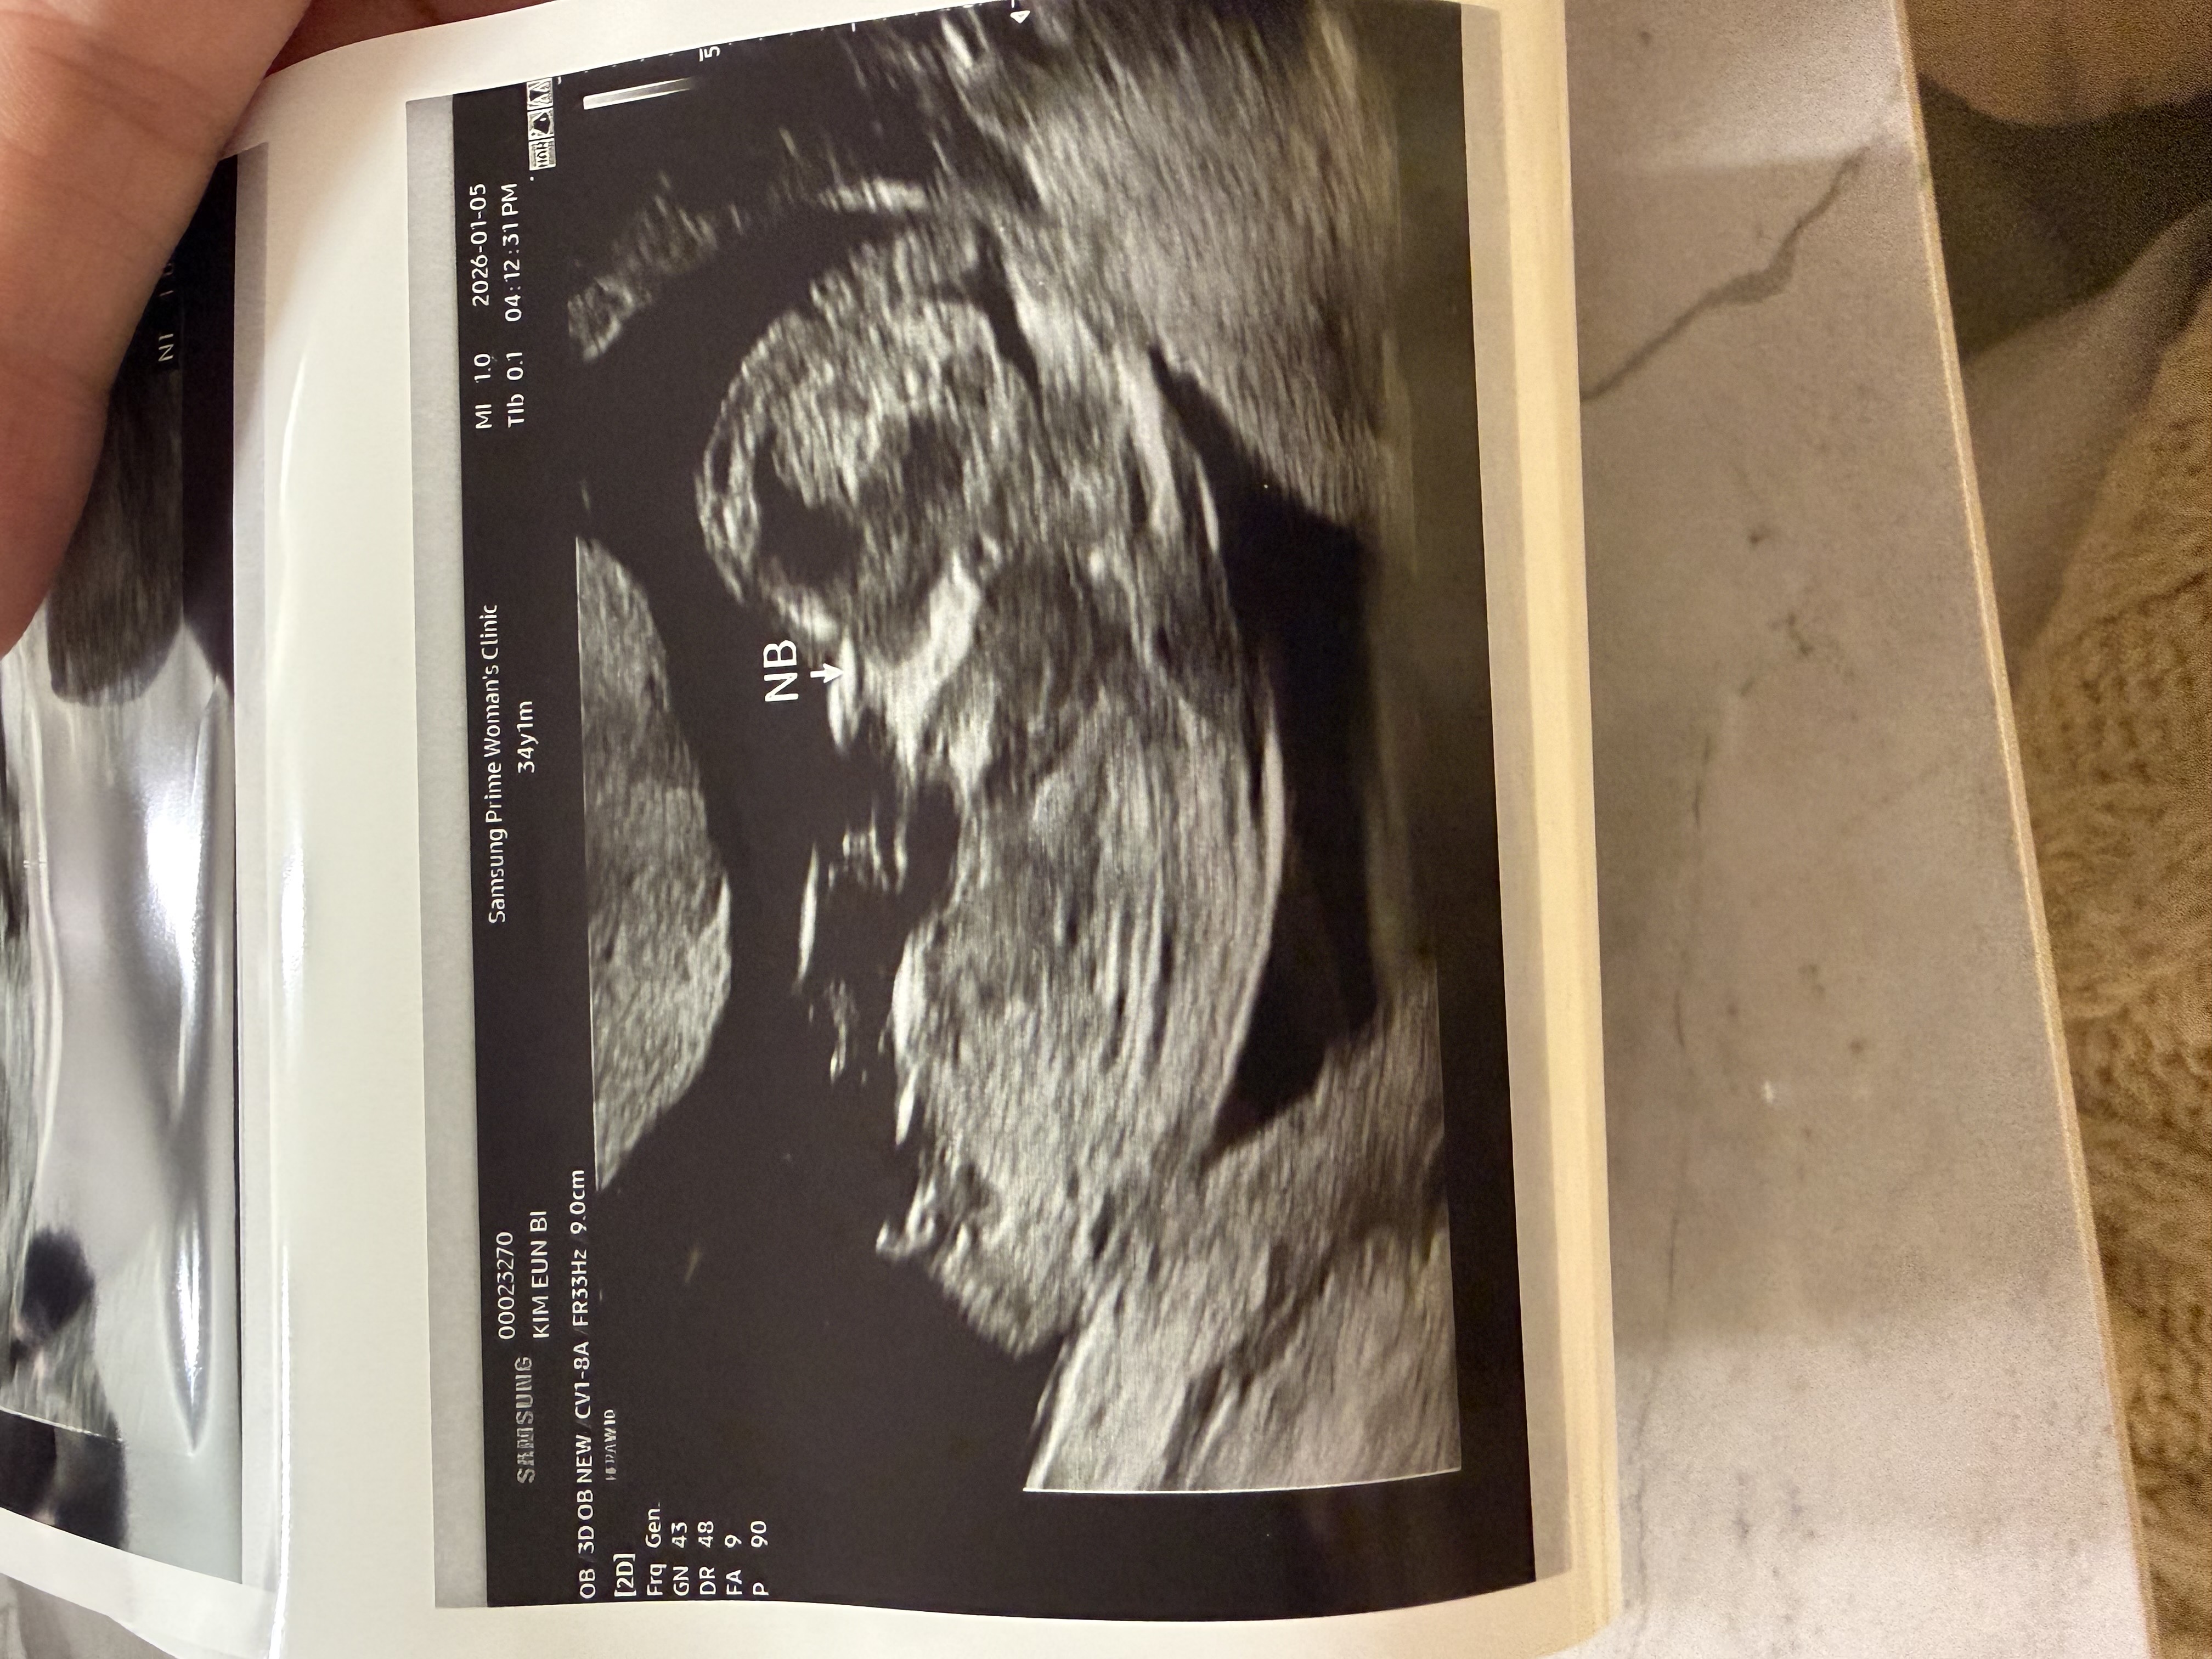

13주1일차 각도법 봐주세요!

각도법으로 딸 아들 투표좀 해주세요! 너무 궁금해요